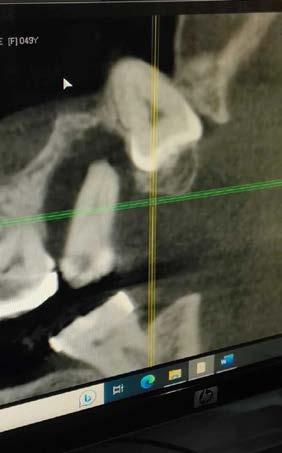

derecho (Figura 1). Especialista en endodoncia solicita cone beam en donde se visualiza lesión periapical extensa que involucra segundo y tercer molar ipsilateral y engrosamiento de la mucosa del seno maxilar sugerente de sinusitis maxilar crónica y su cercanía

con el tercer molar de dicha estructura (Figura 2).

Figura 2. Cone Beam en corte sagital sectorial de segundo y tercer molar.

En un estudio en Latinoamérica por la doctora Novoa, se describe el aumento en los ultimos años de cone beam que tiene una calidad de imagen similar a la tomografía computarizada, con la ventaja de emitir una menor radiación, motivo por el cual fue nuestro elemento diagnóstico en este caso. Al contrario de la radiografía dental que, aunque es el examen radiológico

más usado para detectar periodontitis apical, pero al ser una imagen en 2 dimensiones donde se genera una superposición de estructuras, con una alta tasa de falsos negativos, mientras que la ortopantomografía nos permite ver la neumatización del seno, la relación de los dientes y el seno maxilar, pseudoquistes, restos radiculares y cuerpos extraños intrasinusales, pero también es una imagen en 2 dimensiones.20